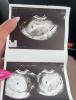

Через три часа еду на узи, я так волнуюсь чтобы он был в матке и вообще был, поспала три часа, спать не могу от слова совсем 😭

@victoria99_, ваааай красота, это про каком хгч/сроке?